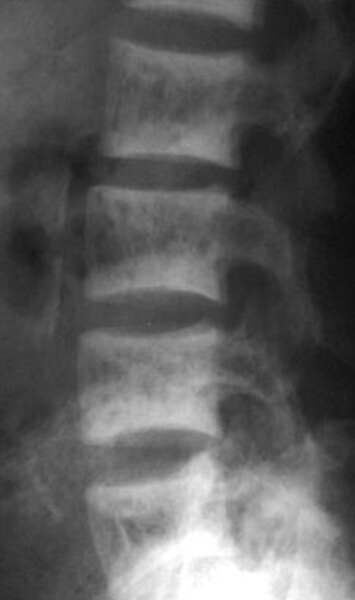

The patient is 70 years old. What is the dianosis? What are the radiographic features you see?

osteoporosis

radiographic features: cortical thinning, resorption of nonstress-bearing trabeculae, accentuated vertical struts, altered vertical shape (codfish deformity), schmorl’s nodes, endplate infractions